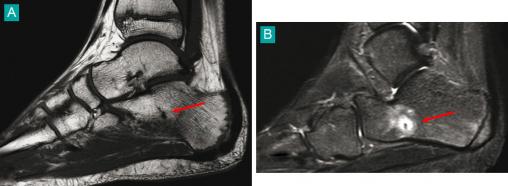

Fracture de fatigue du calcanéum sous forme d'une ligne fine en hyposignal sur les séquences T1 (A), et se rehaussant sur les séquences injectées (B). Voir : P. Journeau, E. Polirzstok, F. Launay, D. Barbier. Lésions osseuses de sollicitation excessive chez l’enfant sportif. Rev Prat 2015;65(8);1084-90.